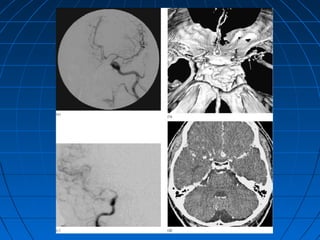

KAROTİKO-KAVERNÖZ FİSTÜLKAROTİKO-KAVERNÖZ FİSTÜL

TANIMTANIM

 A. carotis internaA. carotis interna’nın kavernöz’nın kavernöz

sinüs içinden geçerken verdiğisinüs içinden geçerken verdiği

meningo-hipofizeal dallarınmeningo-hipofizeal dalların

hasarıhasarı ile karotis arteri veile karotis arteri ve

kavernöz sinüs arasında oluşankavernöz sinüs arasında oluşan

arterio-venöz bir fistülarterio-venöz bir fistül

 En önemli nedeniEn önemli nedeni travmatravma,,

spontan da oluşabilirspontan da oluşabilir

 ÇoğunluklaÇoğunlukla ön çukur fraktürleriön çukur fraktürleri

sonucunda görülürsonucunda görülür

KLİNİKKLİNİK

 ÇoğunluklaÇoğunlukla ünilateralünilateral

 Travmayı izleyen günlerdeTravmayı izleyen günlerde

gözdegözde pulsatil egzoftalmi,pulsatil egzoftalmi,

kemozis ve üfürümkemozis ve üfürüm

 Vizyon azalmasıVizyon azalması

 Karotis akımı durdurulursaKarotis akımı durdurulursa

üfürüm kaybolurüfürüm kaybolur

 Spontan olarak iyileşmeSpontan olarak iyileşme

TANITANI

 KlinikKlinik

 ÜfürümÜfürüm

dinlenmesidinlenmesi

 BTBT

 MRG - MRAMRG - MRA

 DSADSA

TEDAVİTEDAVİ

 SAH önlemleriSAH önlemleri

 GirişimselGirişimsel

nöroradyolojinöroradyoloji

 CerrahiCerrahi

MOYA - MOYA HASTALIĞIMOYA - MOYA HASTALIĞI

 İntrakranyal arter sistemininİntrakranyal arter sisteminin

anormal gelişimi ileanormal gelişimi ile ince ağsıince ağsı

damardamarlar oluşumular oluşumu

 ÇokluklaÇoklukla karotis sistemindekarotis sisteminde

 Çocuklar ve genç erişkinlerdeÇocuklar ve genç erişkinlerde

sıksık

 İskemi veya kanamaİskemi veya kanama

 Tanı yolları aynıTanı yolları aynı

 Özel cerrahi girişimlerle tedaviÖzel cerrahi girişimlerle tedavi